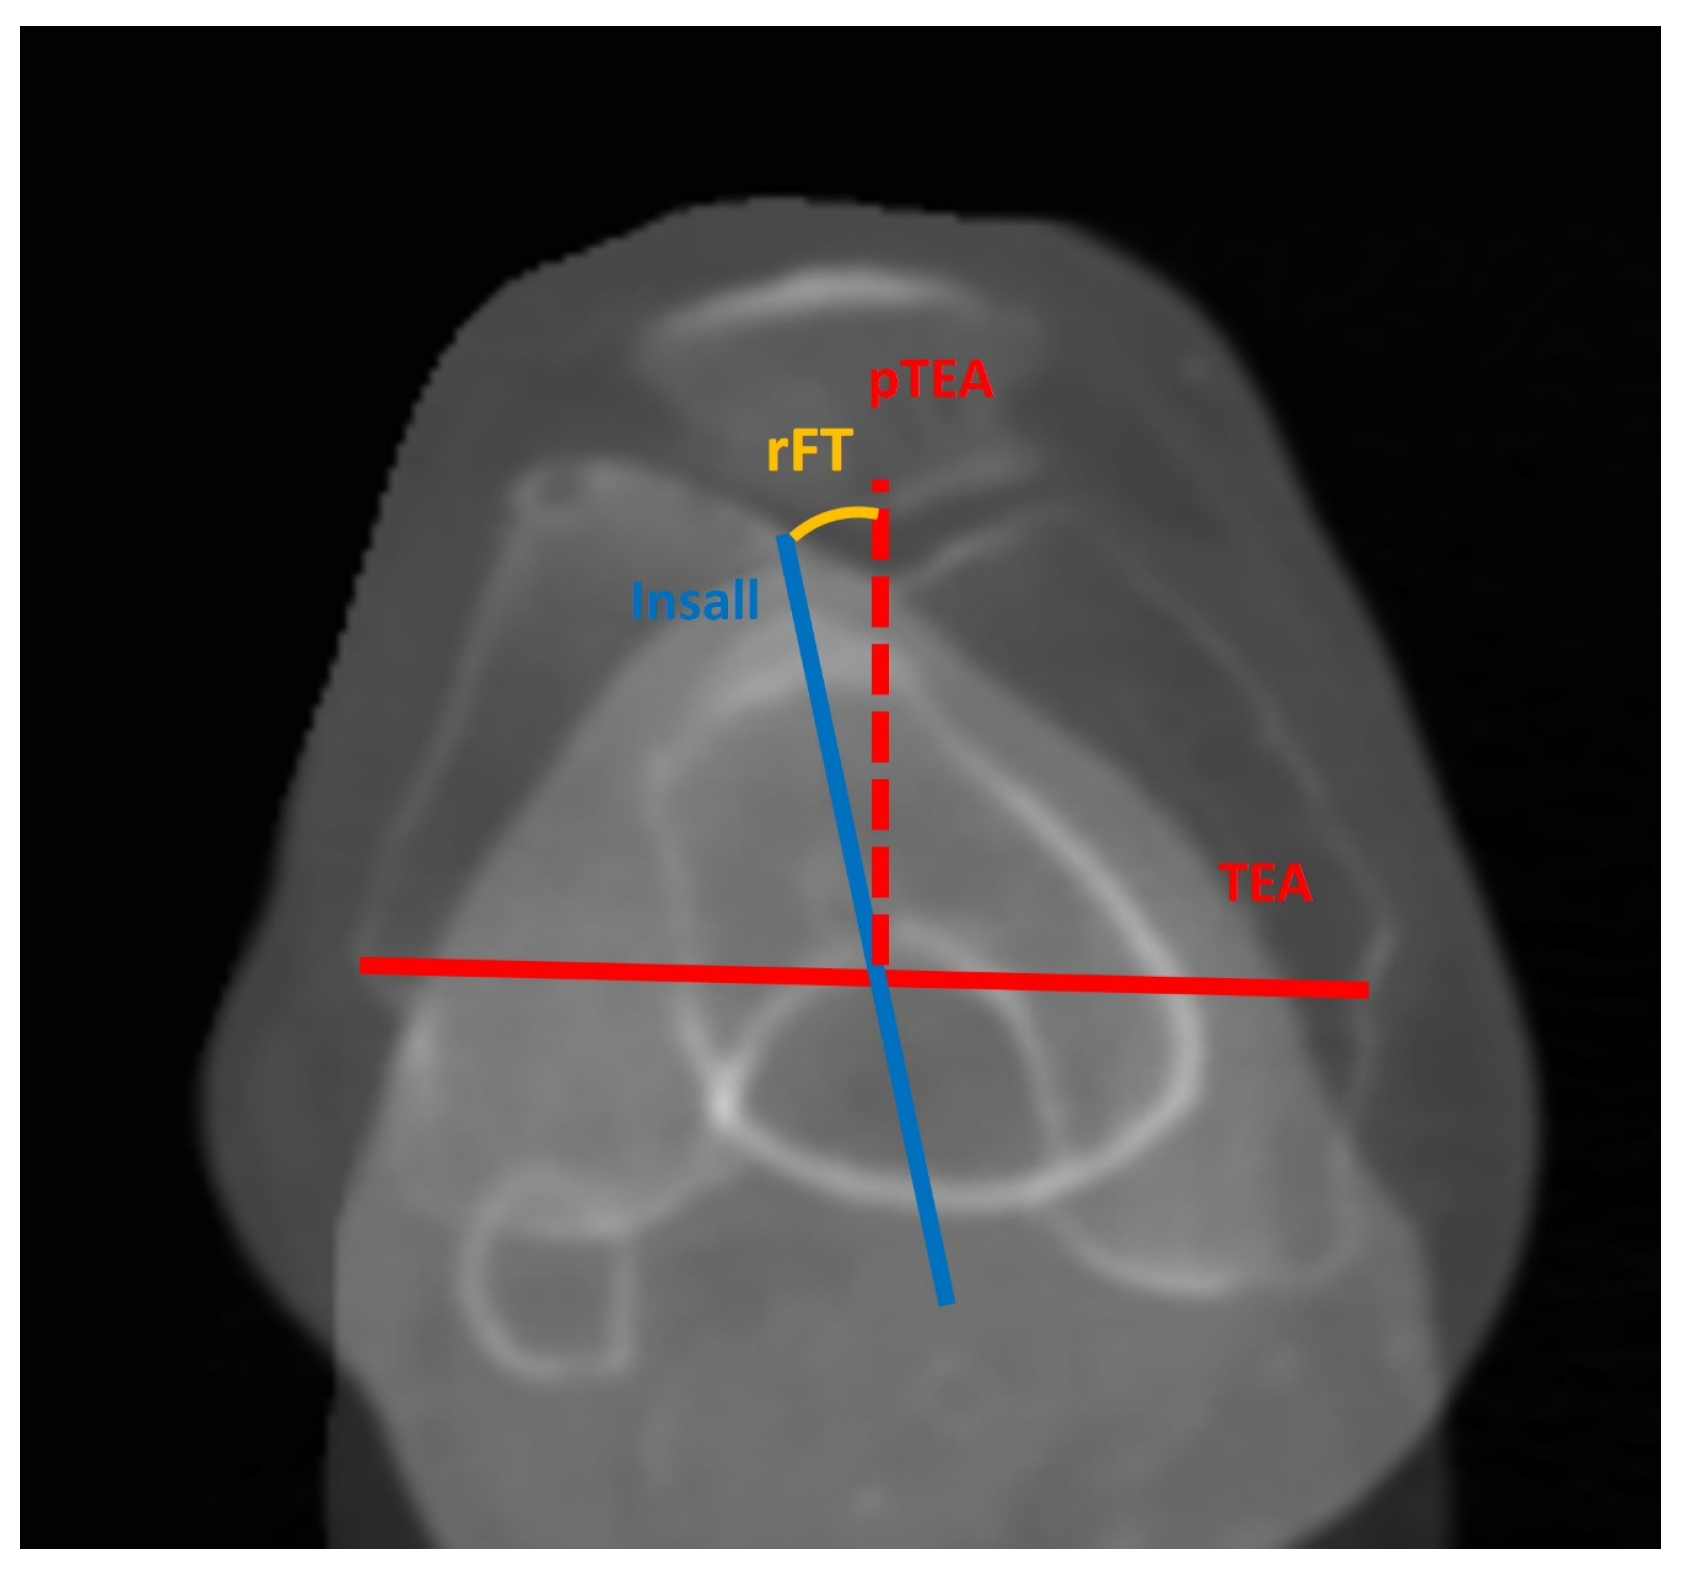

| rFT, ° | −6.7 ± 4.7 (−19.1–3.7) |